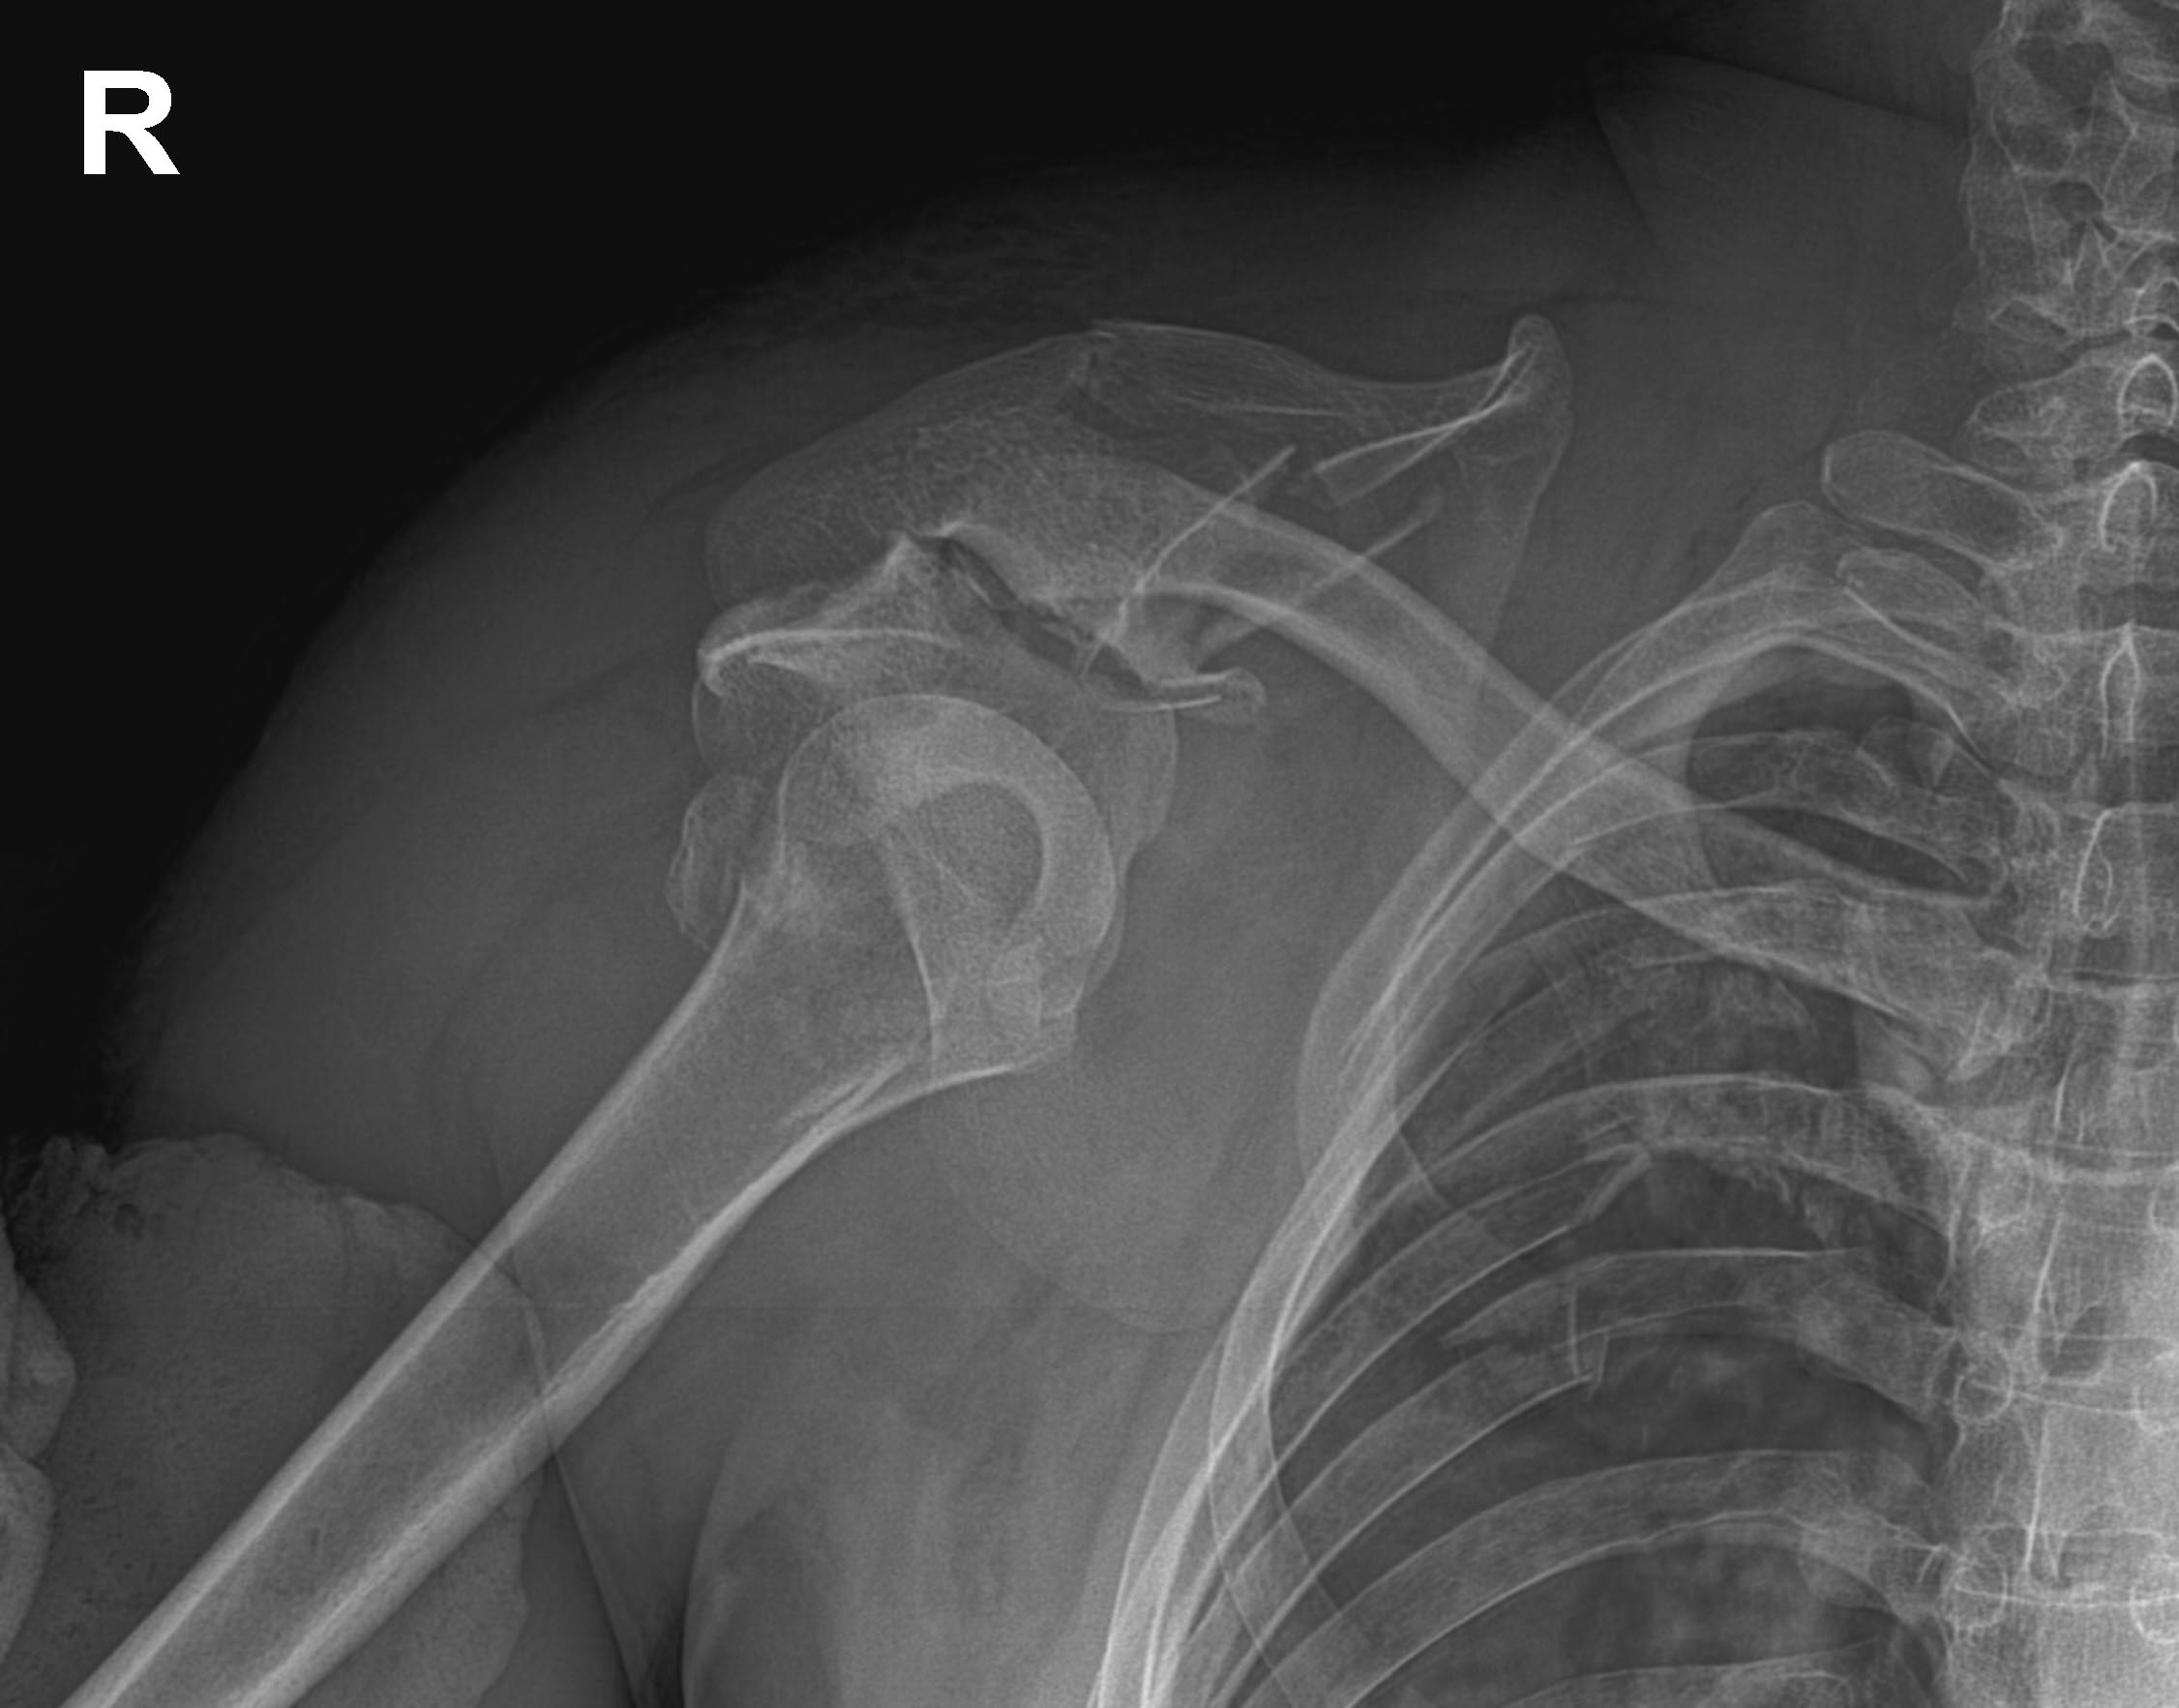

Добрый день, уважаемые коллеги. Поступил мотоциклист 1985 г.р.

Сочетанная травма: множественные переломы ребер справа,

гемопневмоторакс, оскольчатый перелом правой лопатки с вывихом плеча и

вывихом акромиального конца ключицы. Справа же повреждение Монтеджи.

СГМ, ссадины надплечья. Судя по всему, реберно-лопаточная

диссоциация.Помогите, пожалуйста, определиться с тактикой и доступом.